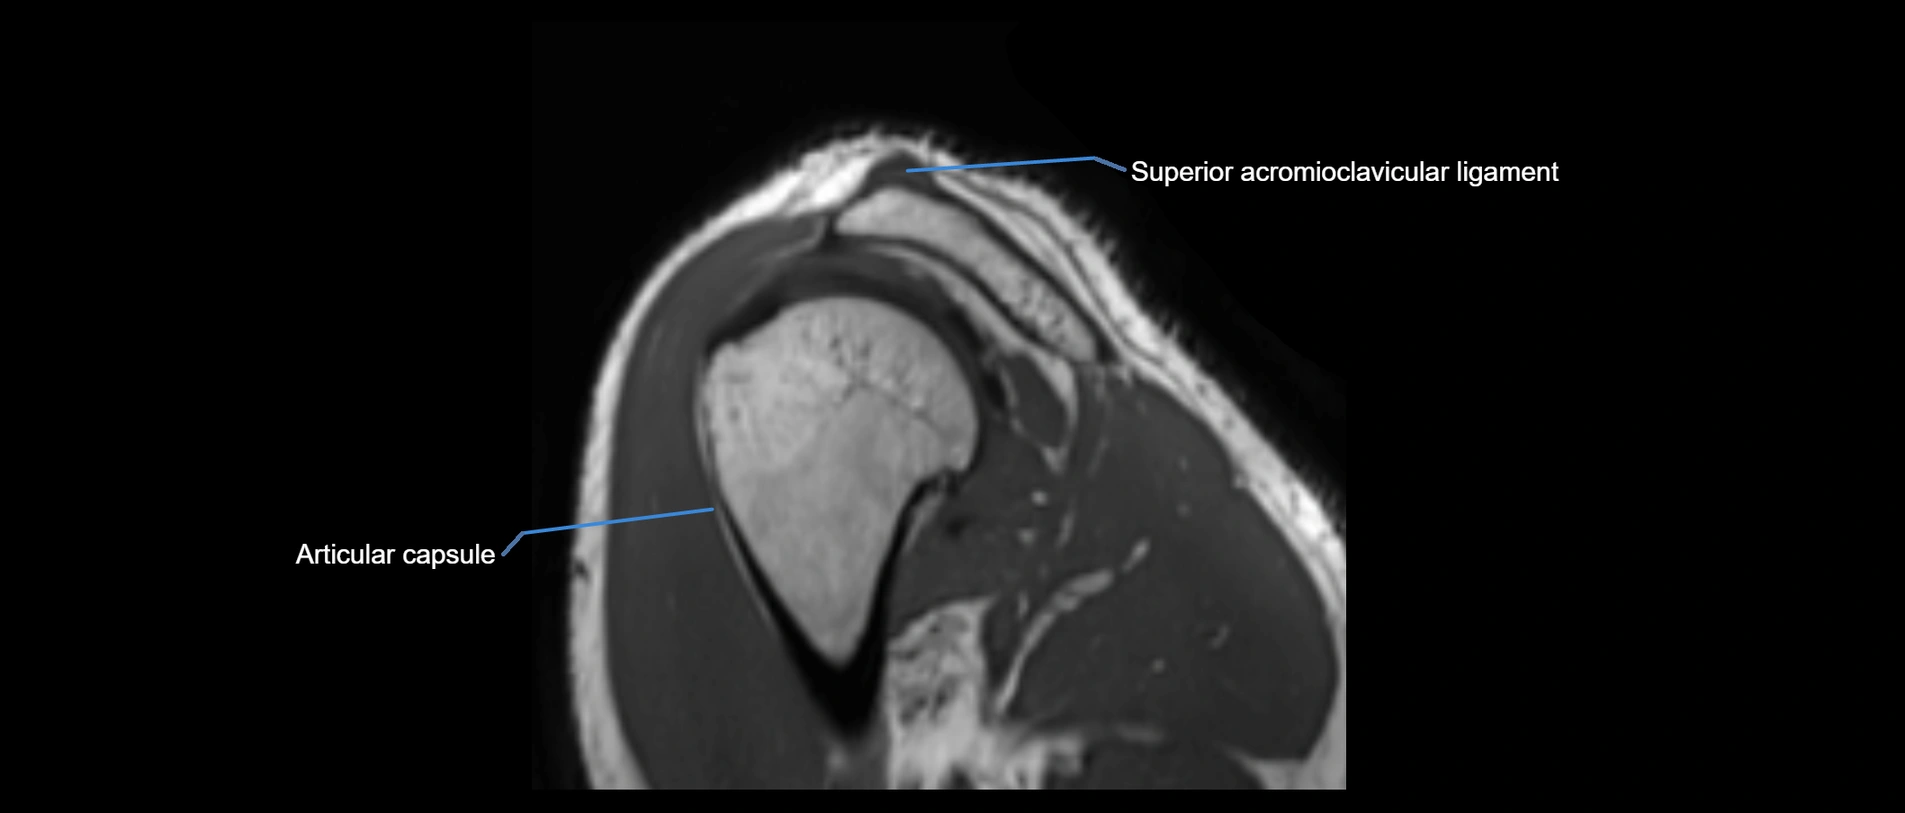

MRI images

image